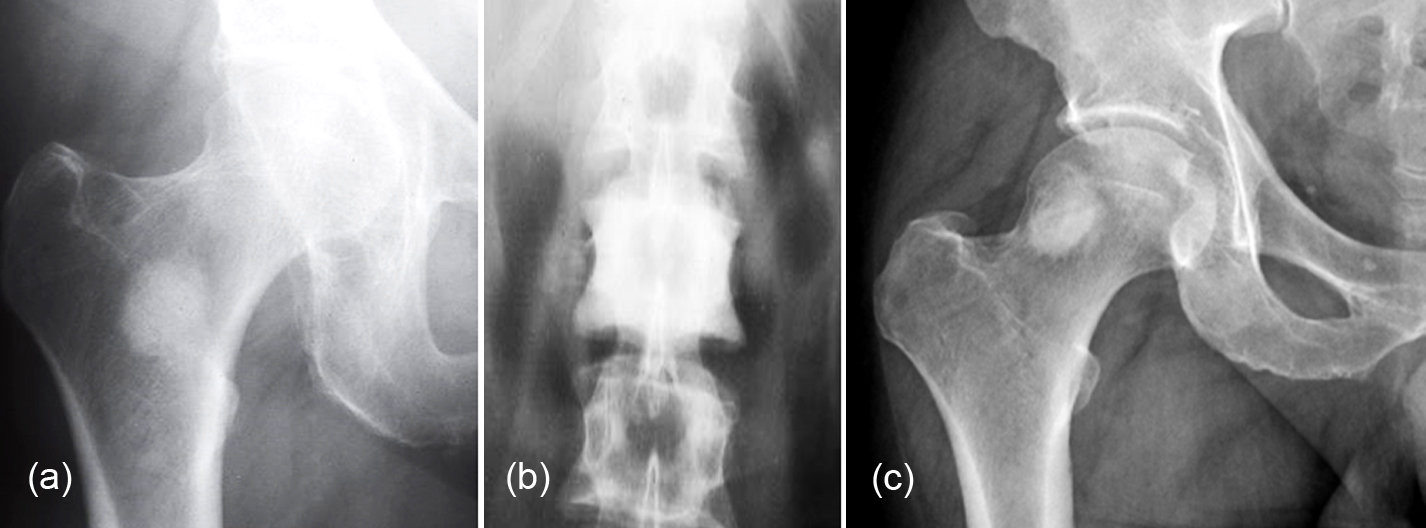

Figure 4h-j: (h) Avascular necrosis femoral head, (I, j) Legg-Calve-Perthes.